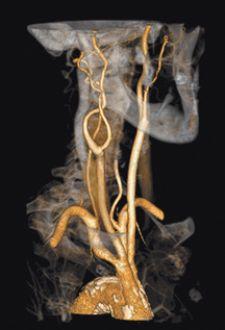

Significant advances have also been achieved in segmentation technologies, which allow clinicians to remove extraneous anatomy during review, but one of the more difficult segmentation challenges is separating small arteries from bone – for example, the deep palmar arch – and isolating this artery using traditional 3-D workstation software tools.

Barco just received FDA 510(k) clearance for CardiaMetrix, its clinical application suite for structural and functional analysis of contrast-enhanced cardiac studies. Integrated into PACS with Voxar 3D and VesselMetrix, a clinical application for quantitative vessel analysis of CTA and MRA, CardiaMetrix’s segmentation and bone removal software is designed to allow users to extract small vessels quickly and provides a 4-D cardiac analysis tool to produce 4-D movies of the beating heart with cardiac contours. The 4-D cine rapidly generates short axis, two-, three- and four-chamber long axis views, semi-automatic alignment with cardiac long axis position and automatic transfer of long axis position in end-diastolic and systolic phases to cardiac (LV) analysis.